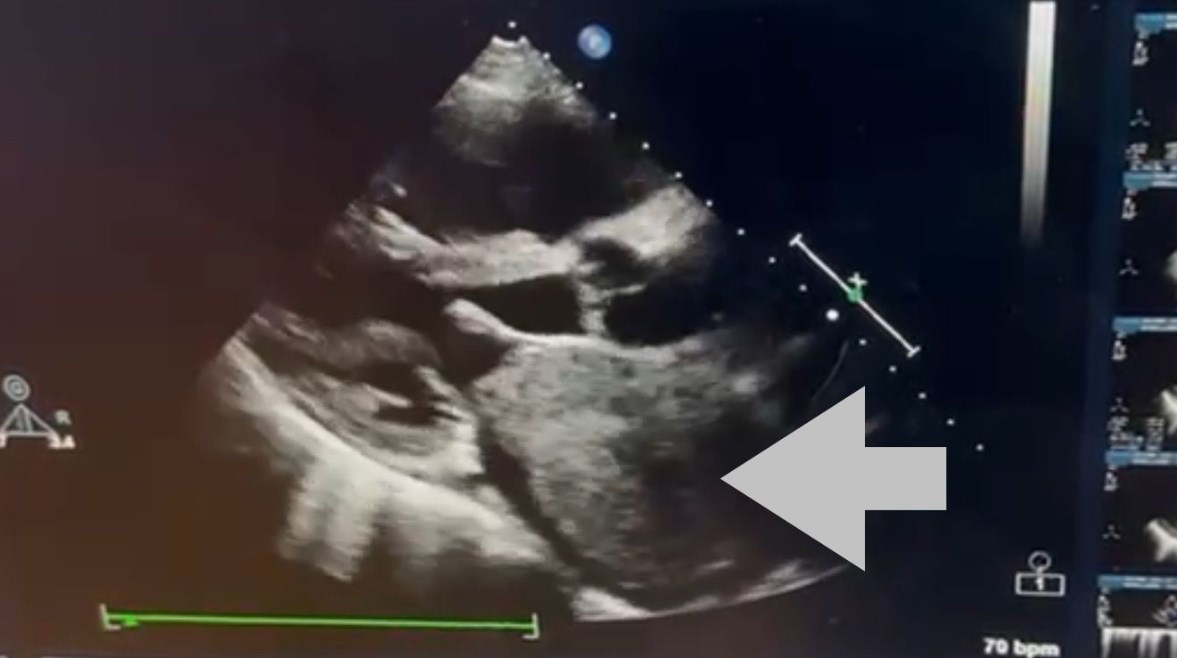

وأوضح الفريق الطبي أن الورم من نوع Cardiac Myxoma، وهو من الأورام القلبية النادرة التي تنشأ داخل حجرات القلب، وقد تسبب في انسداد شديد بفتحة الصمام الميترالي أثناء تدفق الدم، ما أدى إلى ارتفاع ملحوظ في ضغط الشريان الرئوي، نتج عنه ارتجاع شديد بالصمام الثلاثي الشرفات، إضافة إلى تضخم بالأذين الأيسر وحدوث ذبذبة أذينية.

وكان المريض قد وصل إلى المستشفى وهو يعاني ضيقًا شديدًا في التنفس وكحة دموية خلال الفترة الأخيرة، وهي أعراض ناتجة عن تأثير الورم على حركة الدم داخل القلب.

نجاح استئصال الورم وترميم الحاجز الأذيني